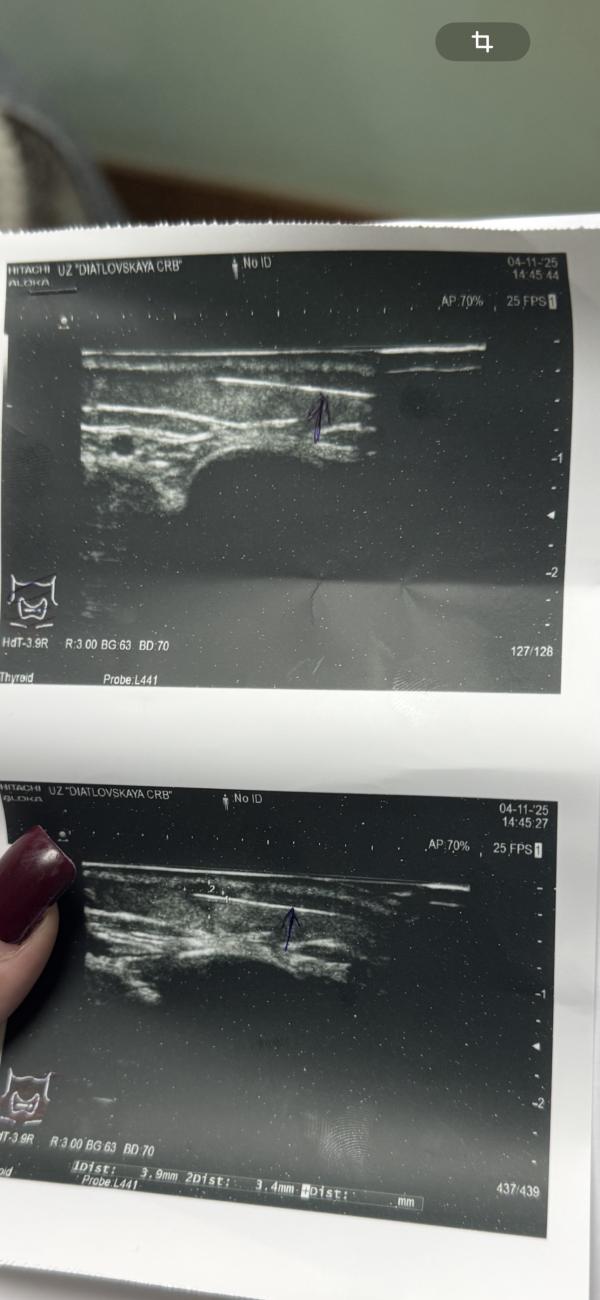

У ребенка на ножке появилось уплотнение ,на узи в этом уплотнение показывает жидкость ,и сверху какая-то полоска ,врач узисит и врач хирург (нашего города) разводят руками ,говорят что может быть инородное тело ,а может спавшаяся полость …хотелось бы еще кого-нибудь нибудь послушать ,может есть хирурги ???

А на узи проявилась не понятная полоска(на фото видно ) и никто точно не знает что это(инородное тело?